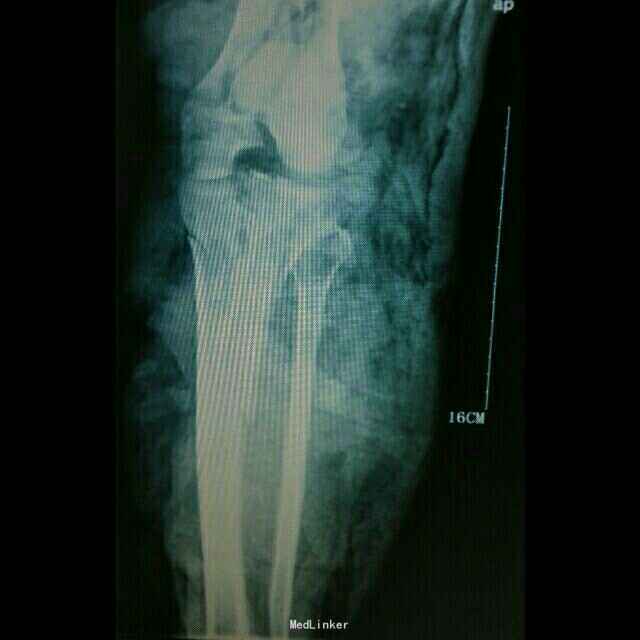

患者,女性,40岁,因车祸伤至左下肢大面积皮肤缺损伴多发粉碎骨折,右足大面积皮肤缺损 急诊入骨科,一期清创,骨牵引 二期拟双下肢截肢,请我科会诊,改行左侧截肢,左足组织移植修复右足

诊断:左下肢毁损伤 右足皮肤软组织缺损 予以行上述手术

术后随访一月半,伤口皮瓣基本存活,部分皮缘坏死,经换药后愈合,康复科功能训练,可拄拐单足站立。 患者出院返回贵州老家,至此失访。